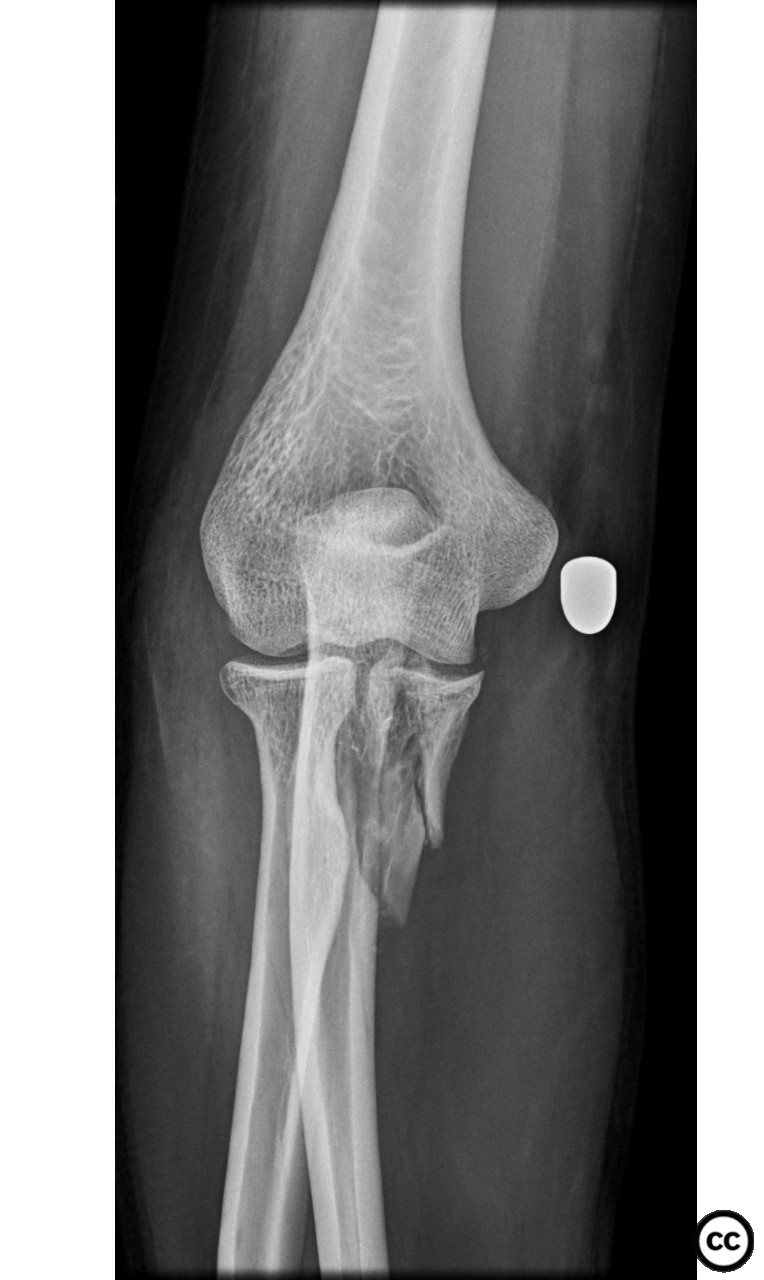

Anteromedial Facet and Sublime Tubercle...

Schleswig Holstein, Germany

Ulna - AO/OTA 2Ux

Sep 27 2024

By Dr Ed Oates

Monteggia Fracture with Segmental Ulna S...

Mar 07 2024

Jupiter IIb Monteggia Fracture-Dislocati...